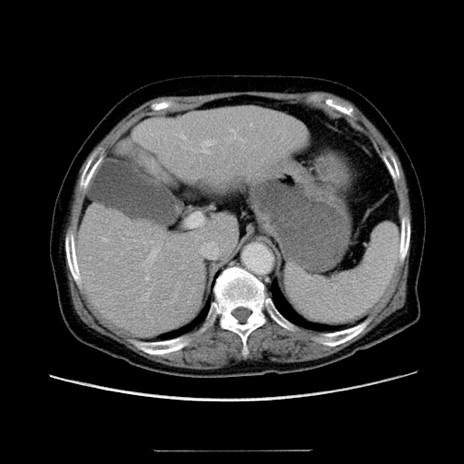

症例5(横断像)

【症例】70歳代女性

【主訴】お腹が張る

【現病歴】1週間くらい前から腹部膨満の自覚あり。昨日夜から増悪したため、本日救急外来受診。

【身体所見】意識清明、BT 36.5℃、BP 165/106mmHg、HR 80bpm、SpO2 98%、腹部:膨満、軟、自発痛・圧痛なし、触診にて不快感あり、腸蠕動音:減弱

【データ】WBC 12600、CRP 1.04